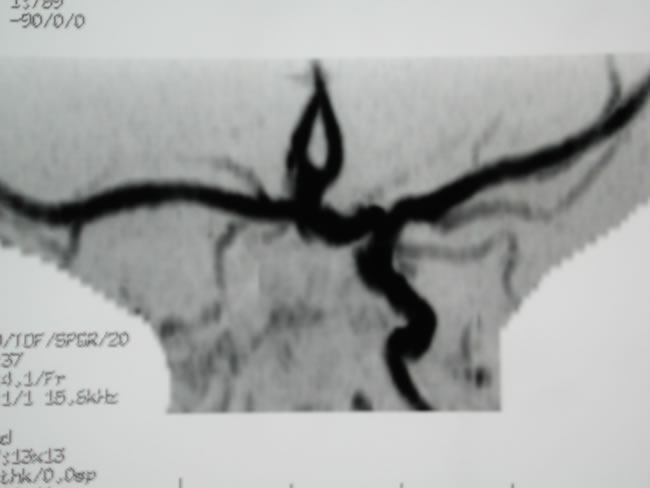

PHACE (anomalia fossa posteriore, angioma, anomalie Arteriose, cardiache, oculari) – Aspetto clinico Figura 4 b

PHACE – angioRMN cerebrale | Figura 5 a